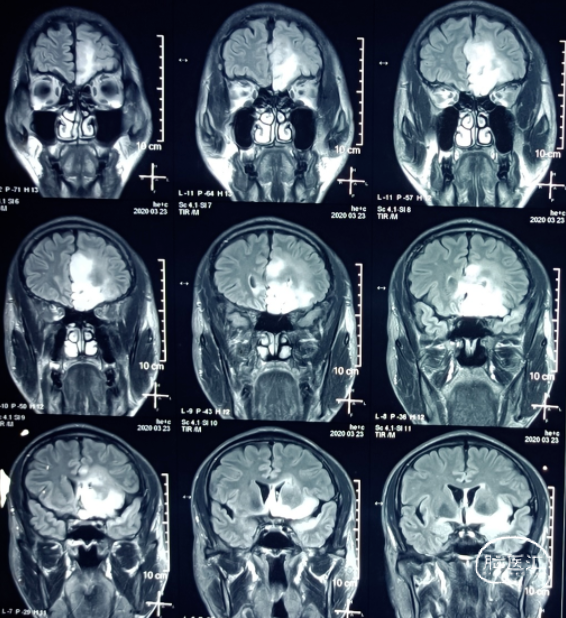

磁共振如下图:

附图:几次磁共振复查显示病变逐渐减小